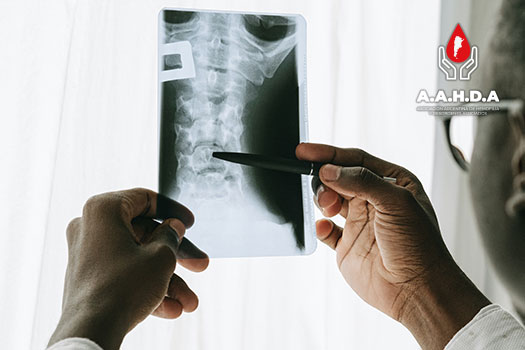

PROTOCOLOS IMÁGEN: RX

ESCALA RADIOLOGICA DE ARNOLD HILGARTNER

Score de Pettersson 240111